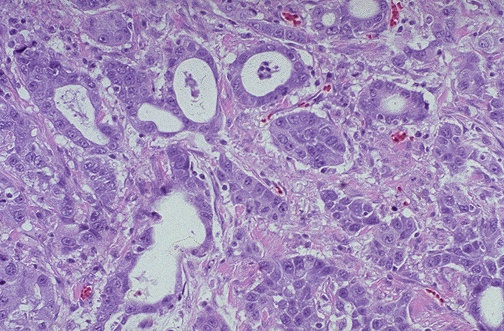

Image 6.5

The microscopic appearance of the lesion is seen here at medium power.